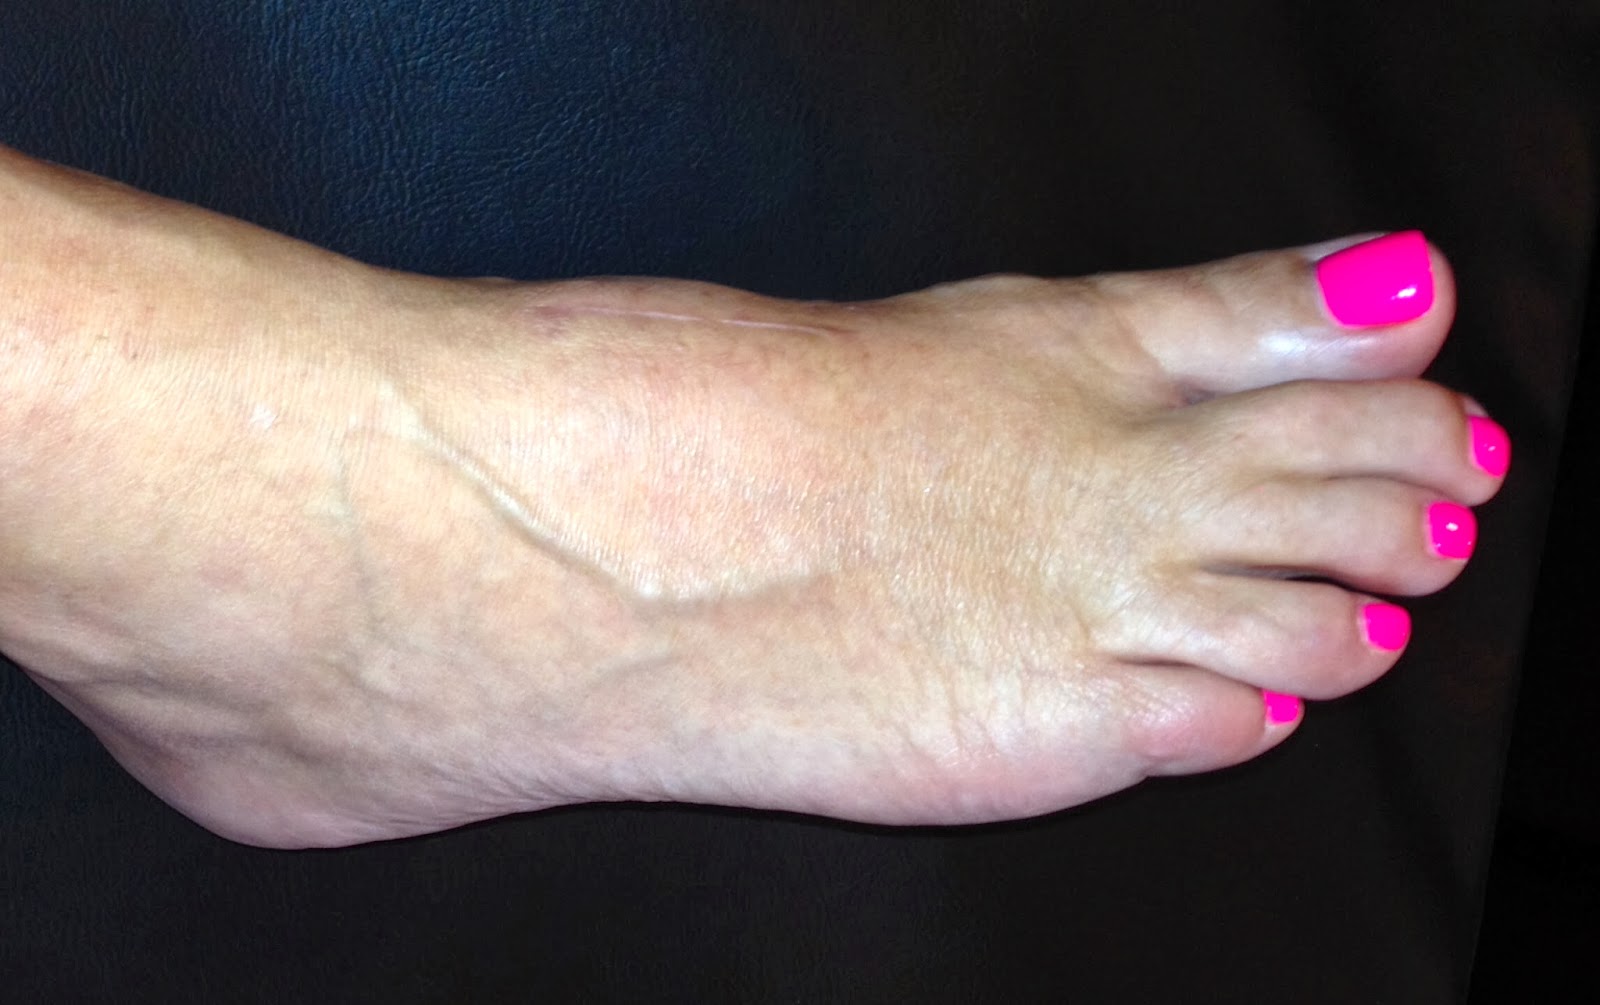

After LisFranc Surgery 23 weeks post lisfranc surgery Recovery After Lisfranc Surgery Web recovery after surgery after reduction of the fracture, your foot will need to be immobilized to allow for the broken. You should elevate the foot as. This protects the bones and incisions. Lisfranc injury can be quite serious and require months to heal. Web what happens after surgery on the lisfranc joint? Web recovering from a lisfranc fracture and. Recovery After Lisfranc Surgery.

After LisFranc Surgery 15 weeks post lisfranc surgery Recovery After Lisfranc Surgery Here's how i coped during the first six weeks, a period of limited. Lisfranc injury can be quite serious and require months to heal. You should elevate the foot as. This protects the bones and incisions. Web what happens after surgery on the lisfranc joint? The foot will be in a cast or a boot, and patients can use a. Recovery After Lisfranc Surgery.

After LisFranc Surgery 10 weeks post lisfranc surgery Recovery After Lisfranc Surgery Web what happens after surgery on the lisfranc joint? For those experiencing strains or sprains, recovery could take six to eight weeks. Here's how i coped during the first six weeks, a period of limited. Web recovering from a lisfranc fracture and surgery takes months, or even years. For those needing surgery, recovery will likely take three to five months.. Recovery After Lisfranc Surgery.

After LisFranc Surgery 25 weeks post lisfranc surgery Recovery After Lisfranc Surgery Web recovery after surgery after reduction of the fracture, your foot will need to be immobilized to allow for the broken. Web overcoming lisfranc injury and reconstructive surgery is one of the biggest challenges some people will ever face. For those needing surgery, recovery will likely take three to five months. Web what happens after surgery on the lisfranc joint?. Recovery After Lisfranc Surgery.

After LisFranc Surgery 22 weeks post lisfranc surgery Recovery After Lisfranc Surgery The foot will be in a cast or a boot, and patients can use a scooter or crutches to keep weight off it. This protects the bones and incisions. You should elevate the foot as. For those needing surgery, recovery will likely take three to five months. Web how long does it take to recover from lisfranc injury? Web recovering. Recovery After Lisfranc Surgery.

After LisFranc Surgery 2013 Recovery After Lisfranc Surgery For those needing surgery, recovery will likely take three to five months. Web overcoming lisfranc injury and reconstructive surgery is one of the biggest challenges some people will ever face. Lisfranc injury can be quite serious and require months to heal. This protects the bones and incisions. Web how long does it take to recover from lisfranc injury? Web recovery. Recovery After Lisfranc Surgery.

After LisFranc Surgery 11 weeks post lisfranc surgery Recovery After Lisfranc Surgery The foot will be in a cast or a boot, and patients can use a scooter or crutches to keep weight off it. For those experiencing strains or sprains, recovery could take six to eight weeks. Web what happens after surgery on the lisfranc joint? Lisfranc injury can be quite serious and require months to heal. Web recovery after surgery. Recovery After Lisfranc Surgery.